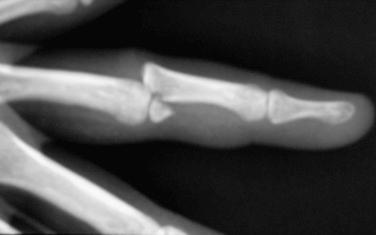

Complex PIP dislocations may present with displaced articular surfaces and bayonet positioning of the phalanges ( Fig. 74.8 ). Rupture of the volar skin can occur from an inside-to-outside mechanism, and residual stiffness is more common after treatment. In the absence of a large accompanying fracture, a closed reduction with anesthesia from a digital block is attempted by gently pushing the middle phalanx (P-2) over the articular surface of the proximal phalanx (P-1). Soft tissues occasionally may become entrapped, necessitating an open reduction through a dorsal approach. The dorsal surgical approach splits the interval between the central slip and the lateral band on one side. Any interposed tissue is extracted and the joint is reduced. Stability is checked after the reduction is performed, and a dorsal splint that blocks terminal extension is fabricated for use in the first 2 to 3 weeks, with the PIP joint in approximately 20 to 30 degrees of flexion. Again, residual flexion contracture is a concern, and active extension is emphasized by 3 weeks. Return to sports, especially if contact is anticipated, is delayed for 3 to 4 weeks with these more severe injuries. Buddy taping or a protective orthosis is recommended during the respective sporting activity until 6 weeks after injury or until nearly full motion is achieved.

Fig. 74.8, The phalanges shown in the bayonet position on anteroposterior x-ray (A) and on lateral x-ray (B).